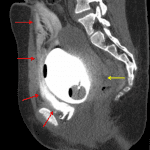

- Wall thickening of the anterosuperior bladder with a possible focal defect and adjacent small amount of low density free intraperitoneal fluid layering dependently in the pelvis

- Right femoral approach venous catheter with tip in the right common iliac vein

- Defect in the anterosuperior bladder with contrast spillage into the peritoneal cavity, layering dependently in the pelvis

- Intraperitoneal bladder rupture

Findings concerning for intraperitoneal bladder with a likely focal defect along the anterosuperior bladder wall. Recommend CT cystogram for further evaluation.

Intraperitoneal bladder rupture with a defect in the anterosuperior bladder wall.